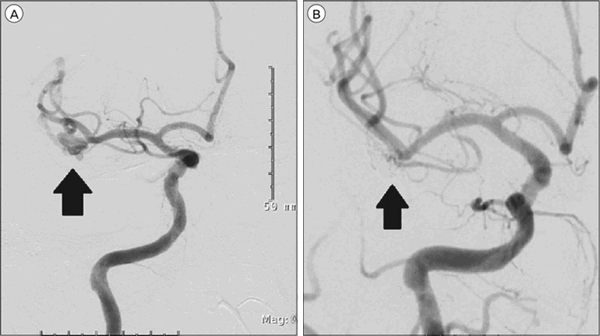

Практикуются открытые хирургические вмешательства. Как это выглядит? После трепанации черепа обнажают артерию, которая является несущей для данной аневризмы, и накладывают на шейку аневризмы специальный клипс. Это называется клипированием аневризмы.

Применяются и эндовазальные (т. е. внутрисосудистые) оперативные вмешательства. Делаются они, как правило, людям преклонного возраста при наличии тяжёлых сопутствующих заболеваний, при труднодоступных аневризмах, при аневризмах, расположенных в чрезвычайно важных функциональных зонах. Они выполняются так: аневризма под контролем рентгена и контрастного вещества заполняется специальными платиновыми микроспиралями, которые «выключают» аневризму из кровотока. Во всём мире в настоящее время всё больше отдают предпочтение именно этому методу: он менее травматичен, даёт меньше осложнений, больные раньше выписываются из стационара. При выполнении ряда эндовазальных вмешательств (для удобства введения в полость аневризмы микроспиралей) могут использоваться специальные стент-ретриверы, которые после выполнения процедуры удаляют.

Оперативное лечение направлено на предотвращение разрыва аневризмы. Его основными методами являются клипирование шейки аневризмы и эндоваскулярная окклюзия. Может применяться стереотаксическая электрокоагуляция и искусственное тромбирование аневризмы при помощи коагулянтов. В отношении сосудистых мальформаций производят радиохирургическое или транскраниальное удаление АВМ.

Слева состояние до операции, справа — после.

Выбор вида оперативного вмешательства зависит от показаний, места локализации, целостности, анатомических особенностей аневризмы сосуда, общего состояния пациента, степени угрозы жизни, технических возможностей нейрохирургического центра. Вмешательство может быть выполнено согласно одной из тактик хирургии.

- Эндоваскулярная операция - в полость сосуда (внутрь) чрескожным доступом (без вскрытия черепной коробки) под рентген-контролем вводится микрокатетер для установки сосудистого стента или спирали. Устройства полностью или субтотально «выключают» артерию из кровотока. Со временем аневризма тромбируется и уменьшается в размерах.

- Микрохирургическая (открытая под контролем микроскопа) - выполняется экономная трепанация черепа с последующим выделением несущей артерии и выполнением окклюзии путем наложения клипсы у основания шейки аневризмы. Клипсирование (сверху сосуда) позволяет пережать аневризматическую шейку, чем исключить из кровотока сосудистый дефект и свести к предельному минимуму вероятность его разрыва.